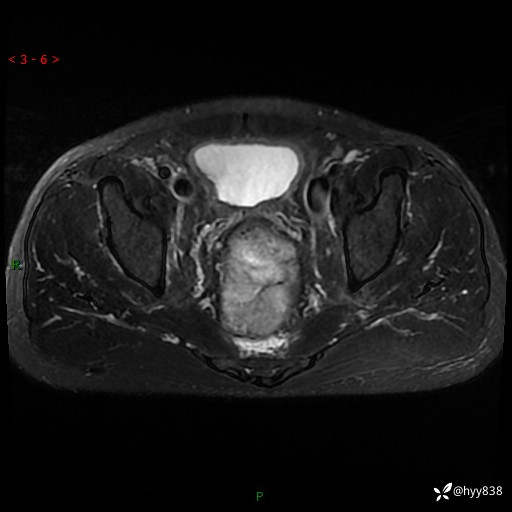

盆腔MRI平扫